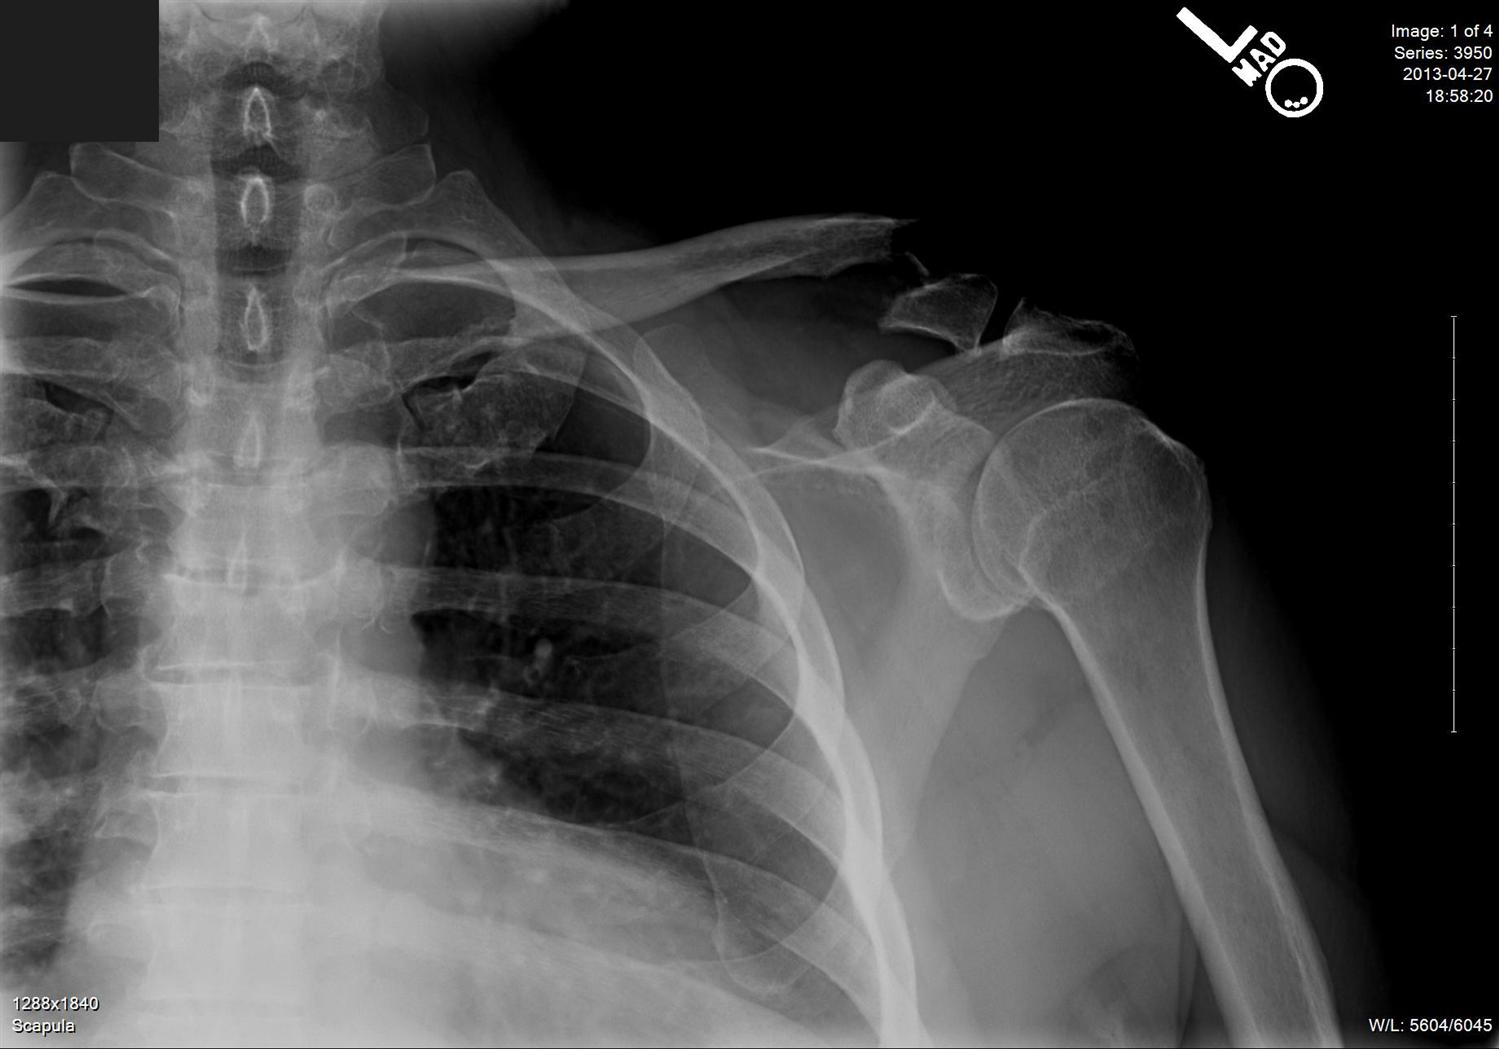

Deforming forces on displaced midshaft clavicle fracture. Download